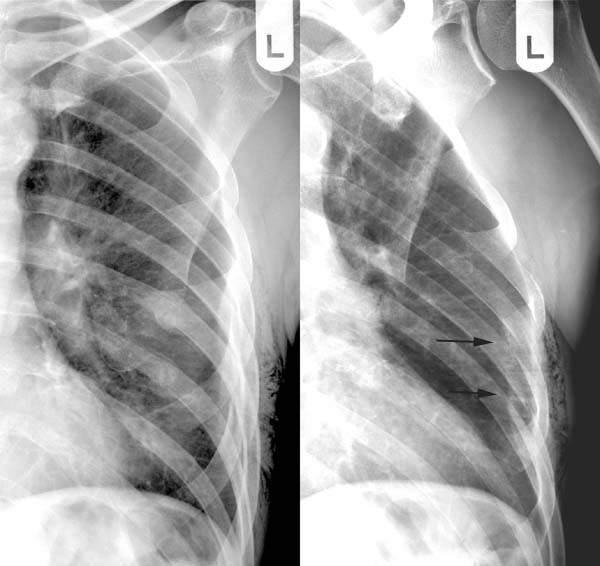

Source: kaiowaskqs.pages.dev Gebrochene Rippen. Farbige Chest XRay zeigt mehrere gebrochene Rippen (orange), unten Mitte , Hierdurch heilen die Bruchenden wieder knöchern zusammen. Wie die Universitätsklinik für Unfallchirurgie Magdeburg erklärt, ist dabei meistens die 4